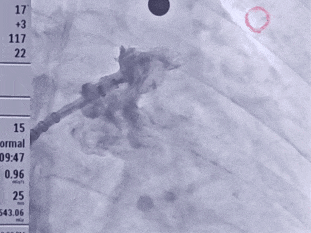

术中DSA肝位造影并测量心耳大小:菜花型左心耳

心耳呈菜花状

开口24.3mm,深度24.7mm

该心耳为菜花型,此类心耳一般多为囊袋状多分叶,术前造影评估远端梳状肌较为发达,开口24.3mm,深度24.7mm,深度足够,建议选择LAFDQ-26封堵器进行封堵。

封堵器展开后造影

封堵器完全展开,封堵器未露肩